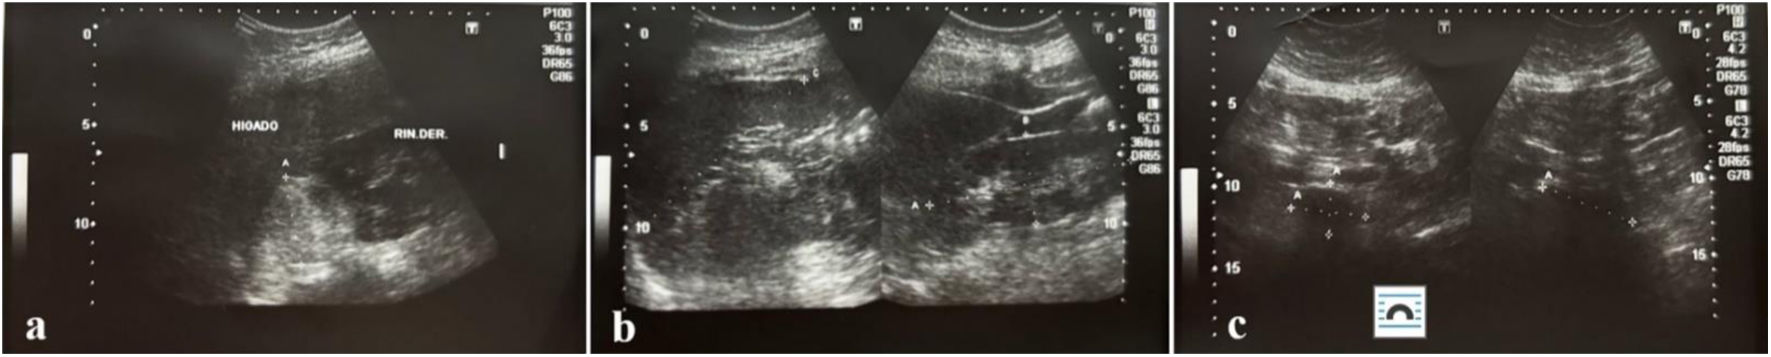

Posteriormente, a los 6 meses, se realizó una ecografía de rutina, en la cual se observó una masa redonda e hiperecoica de 44mm en el espacio hepato-renal, de etiología aún por determinar en la glándula suprarrenal derecha (fig. 1). Se recomendó realizar una tomografía computarizada (TC) abdominal con contraste, la cual describió una tumoración sólida, redondeada, bien definida, de 53×46mm, localizada en la glándula suprarrenal derecha (fig. 2), sin realce tras la administración del medio de contraste. Las estructuras vasculares se encontraron con trayecto y calibre normales, y no se evidenciaron lesiones en las estructuras óseas ni en el retroperitoneo.

Imágenes ecográficas renal y pélvica a los 6 meses de la evaluación inicial. a) Hígado y riñón derecho en forma y situación anatómica normal, bordes regulares y bien definidos, ecoestructura interna homogénea con ecogenicidad dentro de la normalidad b). Se observa en el espacio hepato-renal una masa redondeada a determinar. c) En el espacio hepato-renal, masa redonda hiperecoica de 44mm.